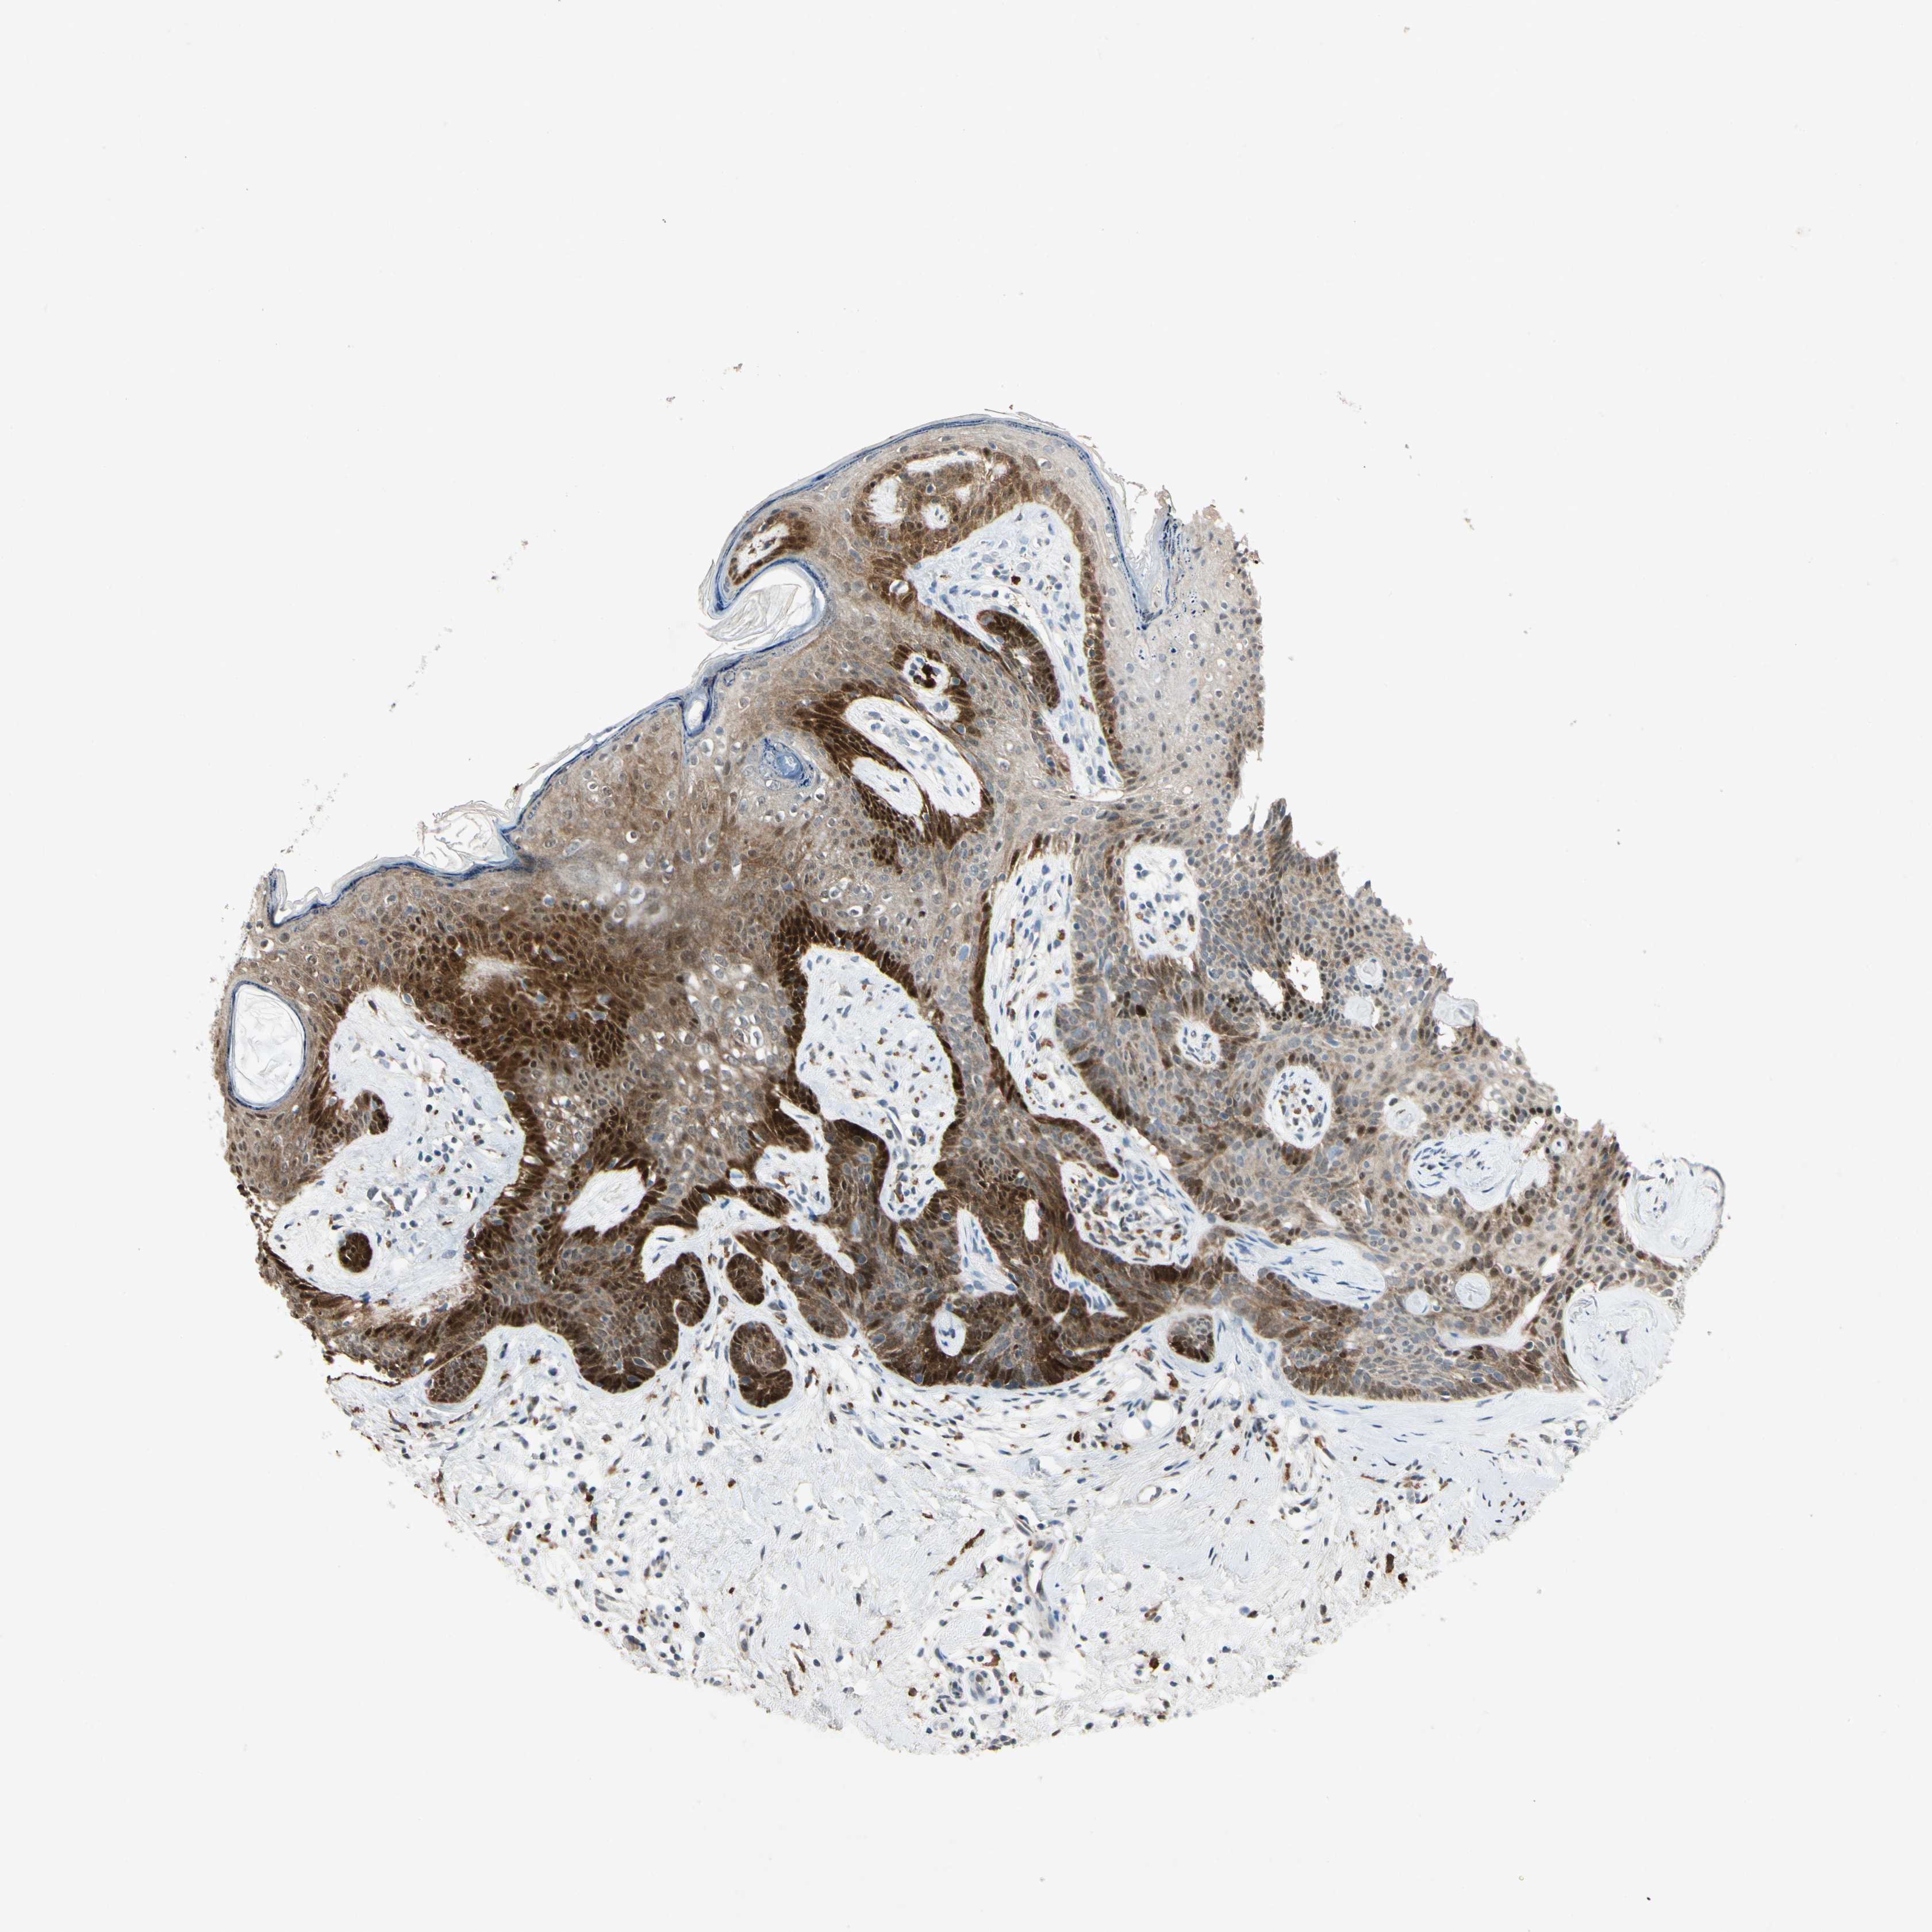

CANCER SKIN CANCER Show tissue menu

Basal cell and squamous cell cancer

SKIN CANCER - Protein expressioni

A mouse-over function shows sample information and annotation data. Click on an image to view it in a full screen mode. Samples can be filtered based on level of antibody staining by selecting one or several of the following categories: high, medium, low and not detected. The assay and annotation is described here.

Each image is clickable and will lead to virtual microscopy that enables deeper exploration of all samples and also displays staining intensity scores, fraction scores and subcellular localization as well as patient and tissue information for each sample.

Antibody HPA052504

Basal cell carcinoma

Squamous cell carcinoma, NOS

Squamous cell carcinoma, metastatic, NOS

Papilloma, NOS